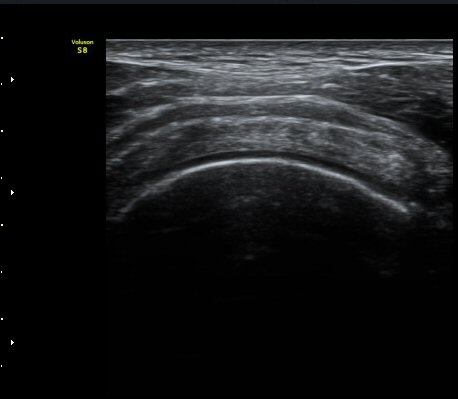

ÀÌµÎ¹Ú±Ù°Ç È¾´Ü¸é°Ë»ç¿¡¼­ ƯÀÌ ¼Ò°ßÀ» º¸ÀÌÁö ¾ÊÀ½(»çÁø 1, 2).

±Ø»ó°Ç Á¾´Ü¸é°Ë»ç¿¡¼­ ´ë°áÀý°ú »ó¿Ï°ñµÎ ÀÌÇàºÎÀ§¿¡ ÇÇÁú°ñ ¿¬¼Ó¼º ¼Ò½ÇÀ» º¸ÀÓ(±×¸² 3, 4, 5)